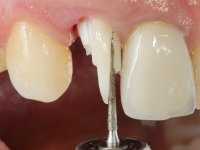

Segunda Fase.

Após 5 anos da primeira intervenção, a paciente surge na consulta com uma peri-implantite nos implantes colocados no local dos dentes 1.2 e 4.6. Começamos por abordar a peri-implantite no local do dente 2.2. Foi feita uma ponte provisória de laboratório em acrílico com 2 elementos. O dente 1.1 como pilar e o 1.2 como pôntico, este último apresentava um apoio distal. A coroa do 1.2 foi removida do coto com um corte longitudinal feito com turbina e depois foi fraturada com um mini luxador. O coto foi de seguida desaparafusado do implante. Fez-se o mesmo procedimento para remover a coroa do 1.1. O dente 1.1 foi re-preparado e a ponte provisória foi rebaseada em boca com acrílico autopolimerizável. Feito o correto acabamento e polimento da provisória foi feita a sua cimentação temporária com cimento de policarboxylato. Numa consulta posterior. foi feita a remoção da ponte provisória, feita a cirurgia para explantação do implante, colocou-se um novo implante e fez-se a regeneração óssea da zona com uma membrana não reabsorvível. 3 meses após foi removida a coroa do implante colocado no 4.6. Foi feito um corte horizontal com turbina na zona cervical e com um mini luxador descolou-se a coroa do coto. Após este procedimento fez-se a explantação do implante. Após 6 meses foi colocado um novo implante no local do 4.6. Após a osteointegração foi feita a impressão com a técnica de moldeira aberta e foi confecionada em laboratório uma coroa aparafusada sobre o implante. Aprovada pela paciente foi apertada definitivamente em boca. Após 1 mês removemos a ponte provisória antero-superior, reforçamos o dente 1.1 com um poste intra- radicular e reconstruimos o coto com uma resina de polimerização dual. Nessa mesma consulta expomos o implante colocado no 1.2 e fizemos uma impressão pela técnica de moldeira aberta com silicone de dupla viscosidade e presa rápida. No laboratório foi feita uma ponte provisória de 2 elementos, aparafusada sobre o implante e cimentada sobre o dente. A primeira ponte provisória foi removida e colocada a segunda aparafusada sobre o implante. A linha de acabamento cervical do 1.1 foi rebaseada com resina composta durante o aperto do parafuso do implante. Depois foi removida, foram feitos os acabamentos e finalmente apertada sobre o implante e cimentada temporariamente sobre o dente. Após 2 meses de maturação dos tecidos moles em função do perfil de emergência criado pela nova ponte provisória, pudemos avaliar a estética conseguida em conjunto com a paciente. Neste longo processo o dente 2.1 teve que fazer um tratamento endodôntico. Decidiu-se assim fazer também uma coroa no dente 2.1.O dente 2.1 foi preparado na mesma consulta em que se fez a impressão ao implante. A ponte provisória foi utilizada para individualizar a peça de transferência, copiando o seu perfil de emergência e em seguida foi realizado o afastamento gengival com caolino. A impressão foi feita com a técnica de moldeira aberta com silicone de dupla viscosidade e presa rápida. Após a escolha da cor, a impressão foi enviada  para o laboratório onde foram confecionadas 2 coroas  com infraestrutura em Zr. revestidas a cerâmica para os dentes 1.1 e 2.1 e uma coroa aparafusada sobre o implante no dente 1.2. O trabalho final foi aprovado pela paciente e foi colocado definitivamente em boca. A coroa sobre o implante foi aparafusada com 35 N e as coroas foram cimentadas com cimento de ionómero de vidro reforçado com resina.